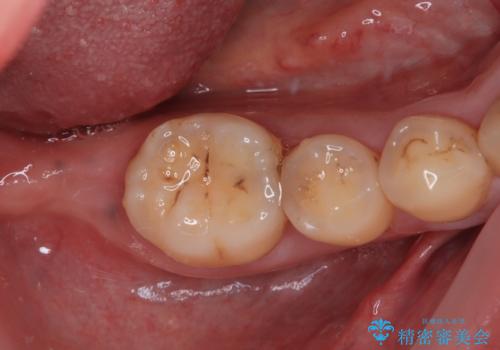

- 左下欠損部のインプラント治療を希望して来院された患者様です。

左下の欠損部を長期間欠損を放置していたことで、咬み合う上の奥歯が動いてしまっていたので、まずは上顎奥歯の部分矯正を行うこととしました。

理想的な咬み合わせに改善した上で、インプラント補綴治療を行うこととしました。